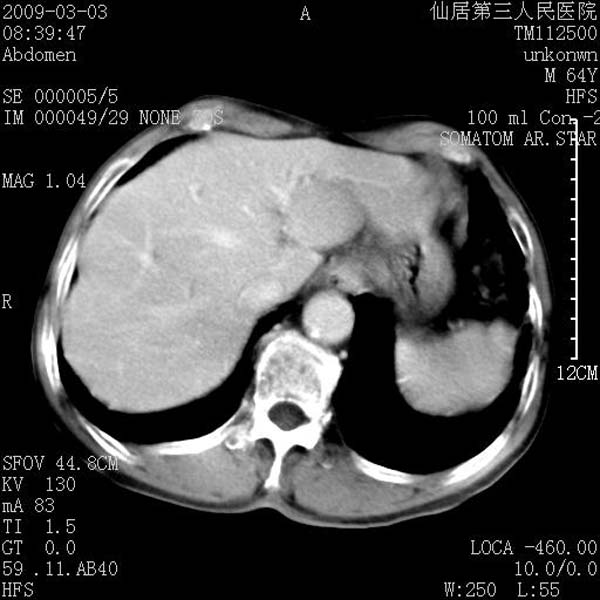

标题: CT18469:男性,64y,体检B超示肝脏低回声肿块,有胃溃疡手术 [打印本页]

患者,男性,64y,体检b超示肝脏低回声肿块,有胃溃疡手术史。

考虑----胃肠道间质瘤可能性大

从平扫及增强的特点来看,支持肝脏腺瘤并出血。

考虑胃间质瘤可能性大。

胃肠道间质瘤!

ct值呢?感觉没强化,象囊性。

考虑肝静脉韧带裂区良性占位性病变(囊肿?)。

考虑肝囊肿并出血可能性大.

考虑高密度囊肿可能性大